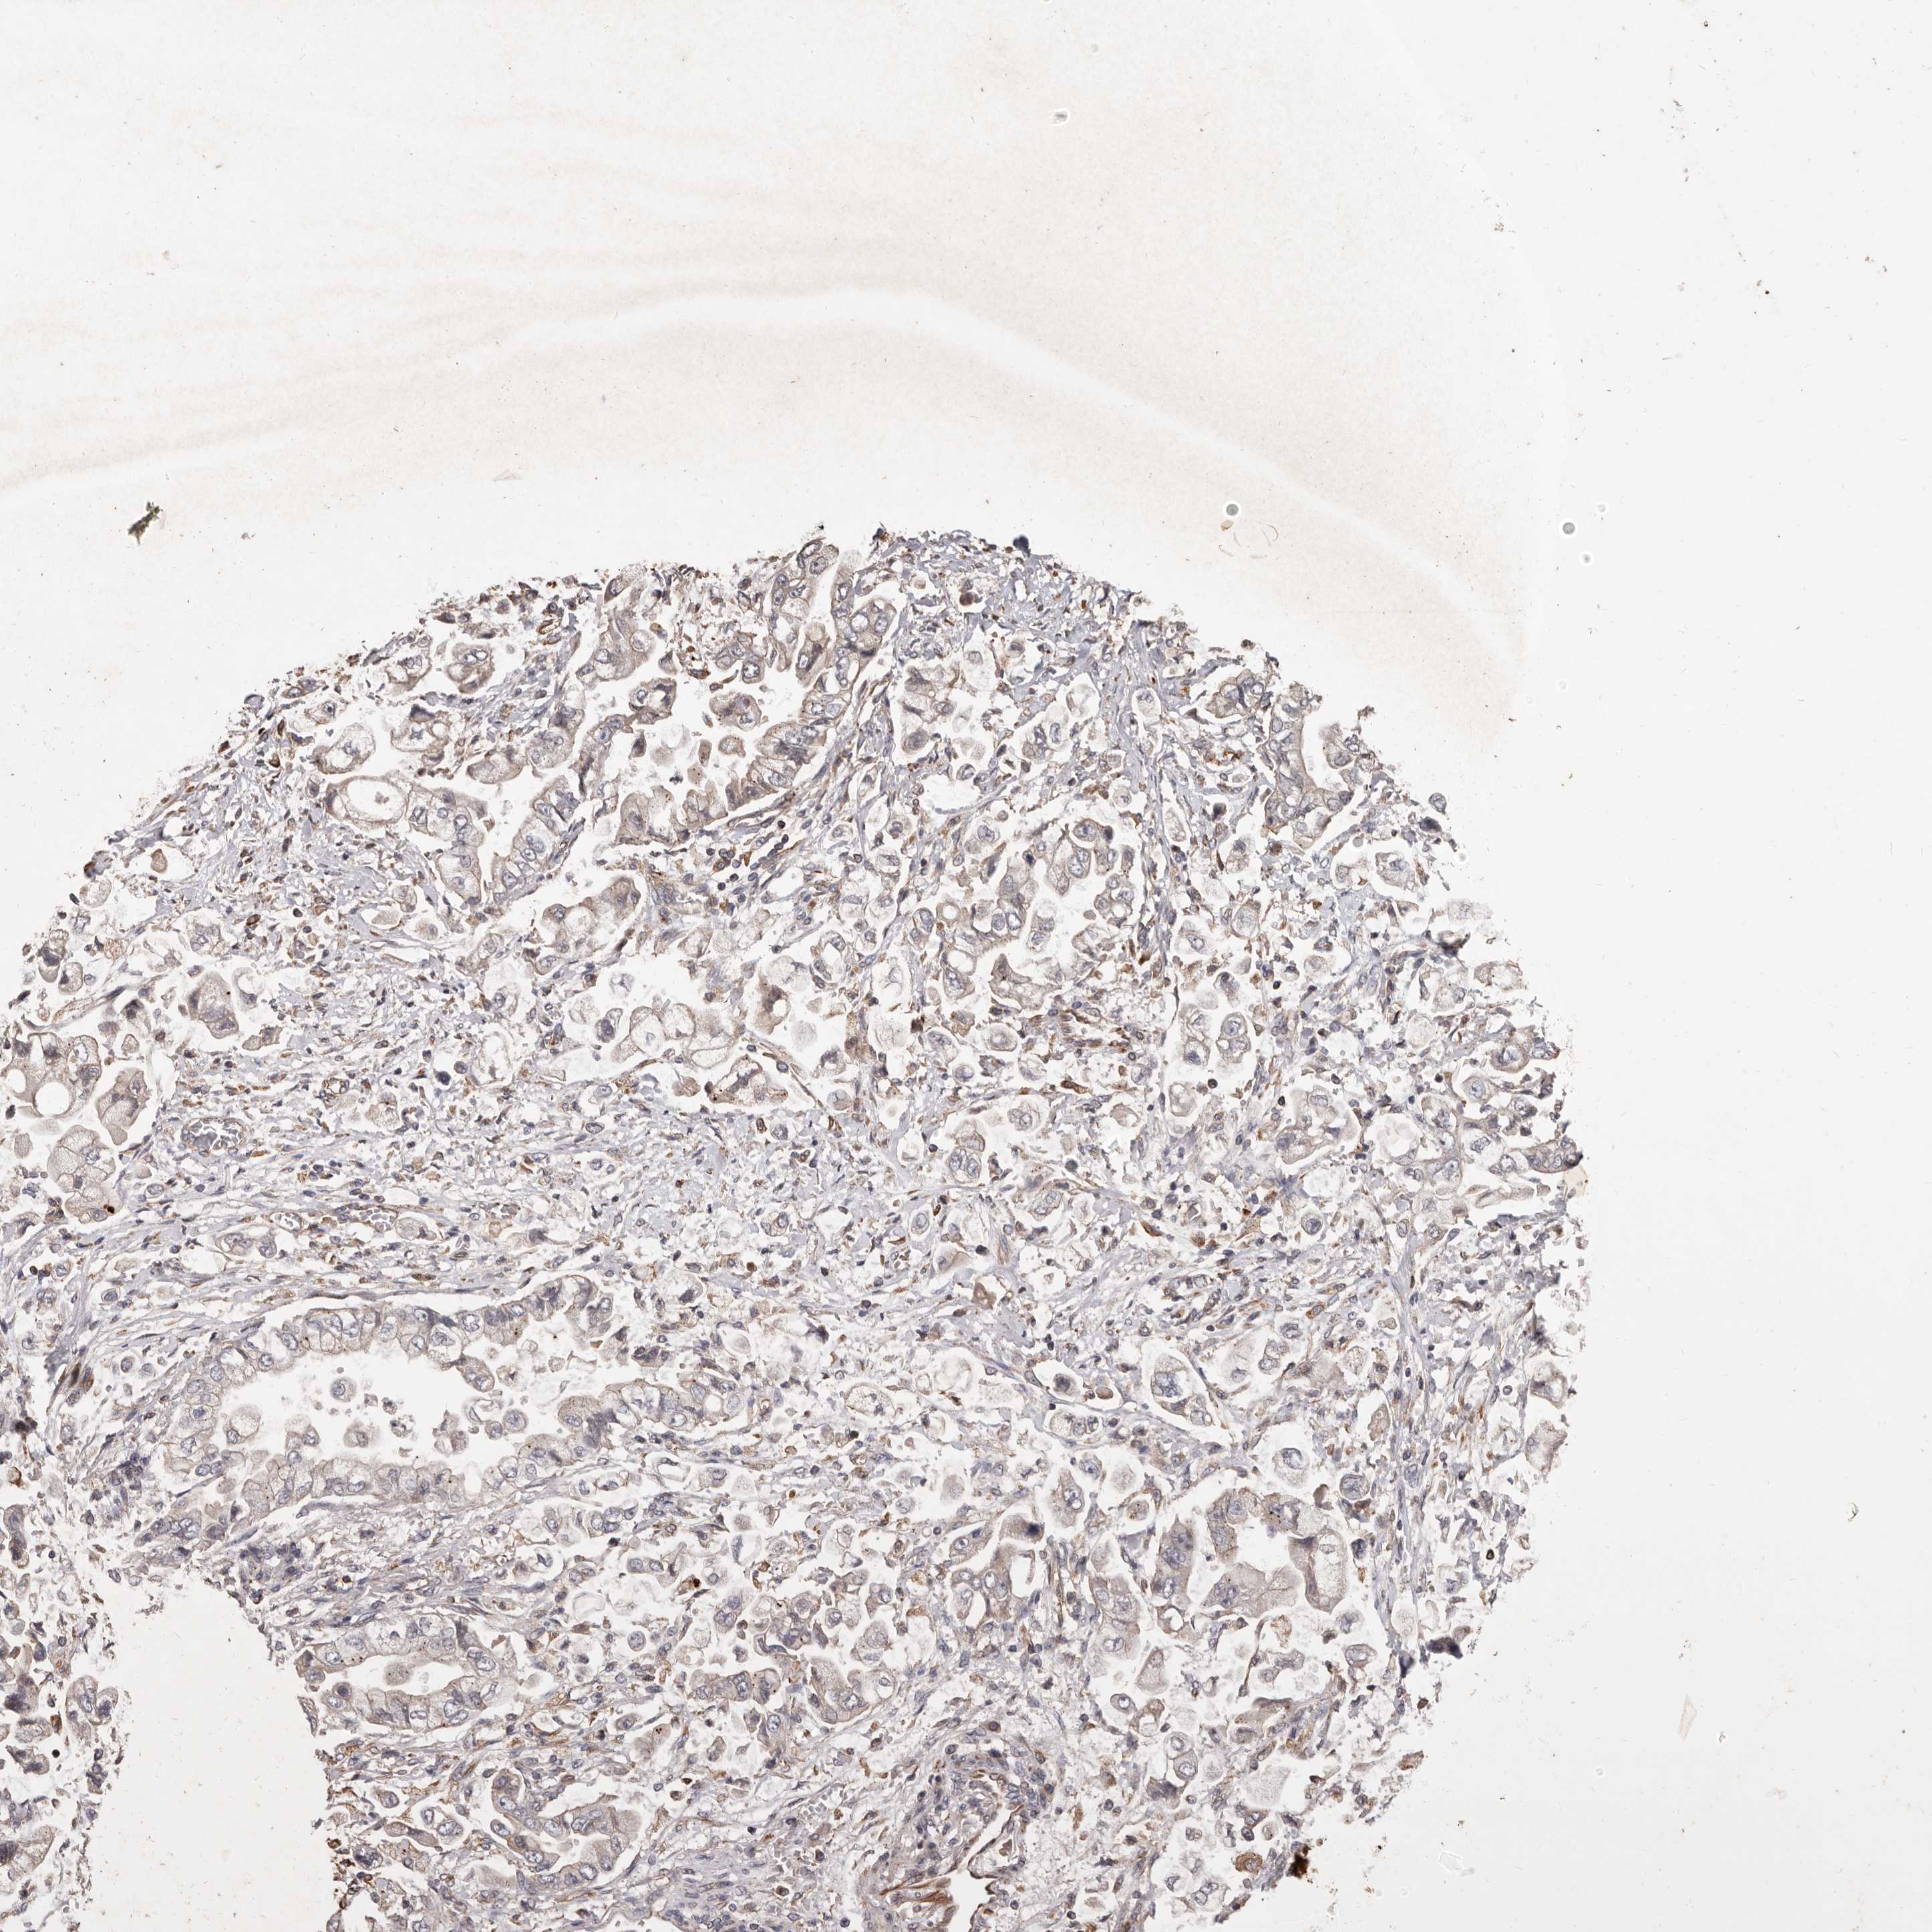

STOMACH CANCER - Protein expressioni

A mouse-over function shows sample information and annotation data. Click on an image to view it in a full screen mode. Samples can be filtered based on level of antibody staining by selecting one or several of the following categories: high, medium, low and not detected. The assay and annotation is described here.

Note that samples used for immunohistochemistry by the Human Protein Atlas do not correspond to samples in the TCGA dataset.

Antibody stainingi

Antibody staining in the annotated cell types in the current human tissue is reported as not detected, low, medium, or high, based on conventional immunohistochemistry profiling in selected tissues. This score is based on the combination of the staining intensity and fraction of stained cells.

Each image is clickable and will lead to virtual microscopy that enables deeper exploration of all samples and also displays staining intensity scores, fraction scores and subcellular localization as well as patient and tissue information for each sample.

Antibody HPA029455

Staining

High

Medium

Low

Not detected

Intensity

Strong

Moderate

Weak

Negative

Quantity

>75%

75%-25%

<25%

None

Location

Nuclear

Cytoplasmic/membranous

Cytoplasmic/membranous,nuclear

Adenocarcinoma, NOS